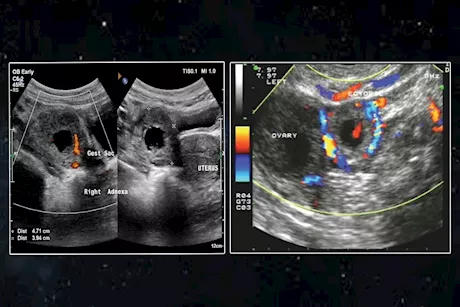

الحمل خارج الرحم.. أعراضه وأسبابه وعلاجه

يستعرض "الكونسلتو" في التقرير التالي، أسباب الحمل خارج الرحم وأعراضه ومتى يحدث وطرق علاجه.